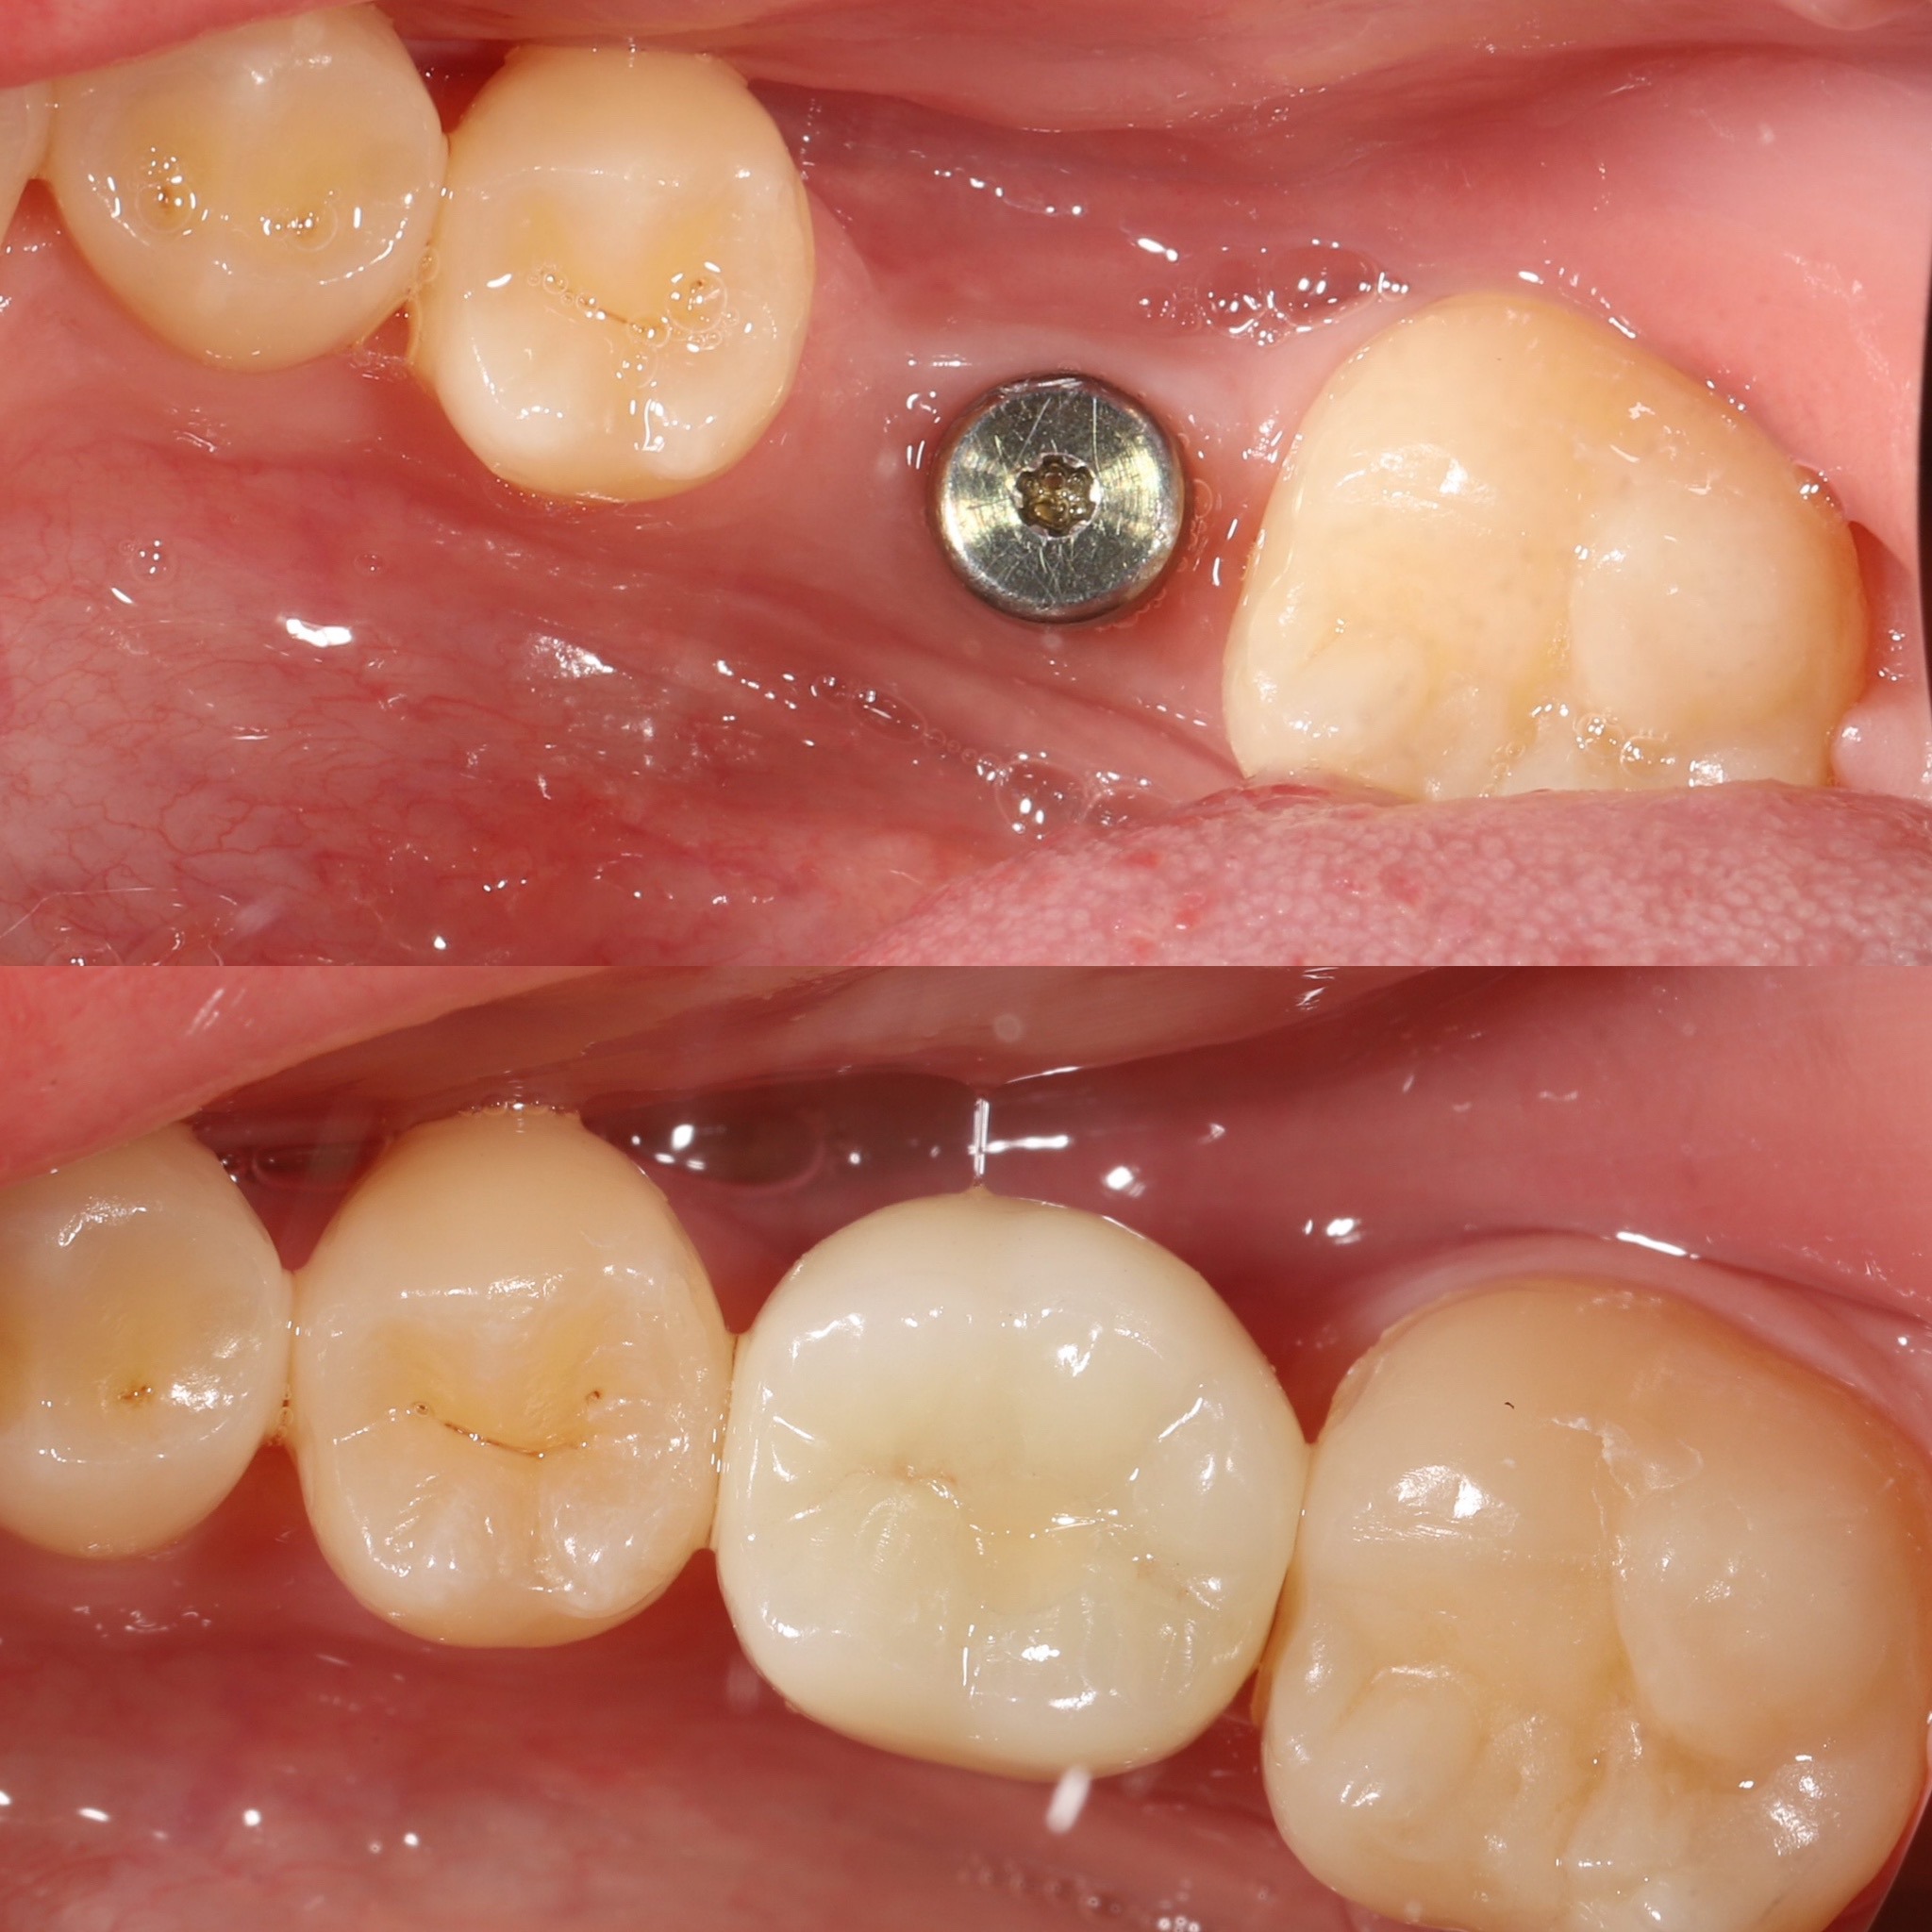

Зубний імплант складається з трьох частин:

• Титановий стрижень — замінює корінь зуба та вживлюється у кістку.

• Абатмент — з’єднувальний елемент між імплантом і коронкою.

• Коронка — видима частина, що повторює форму й колір натурального зуба.

3. Остеоінтеграція — період зрощення імпланта з кісткою, що триває 2–6 місяців.

4. Установка абатмента та коронки — завершальний етап, після якого пацієнт отримує міцний і повноцінний зуб.